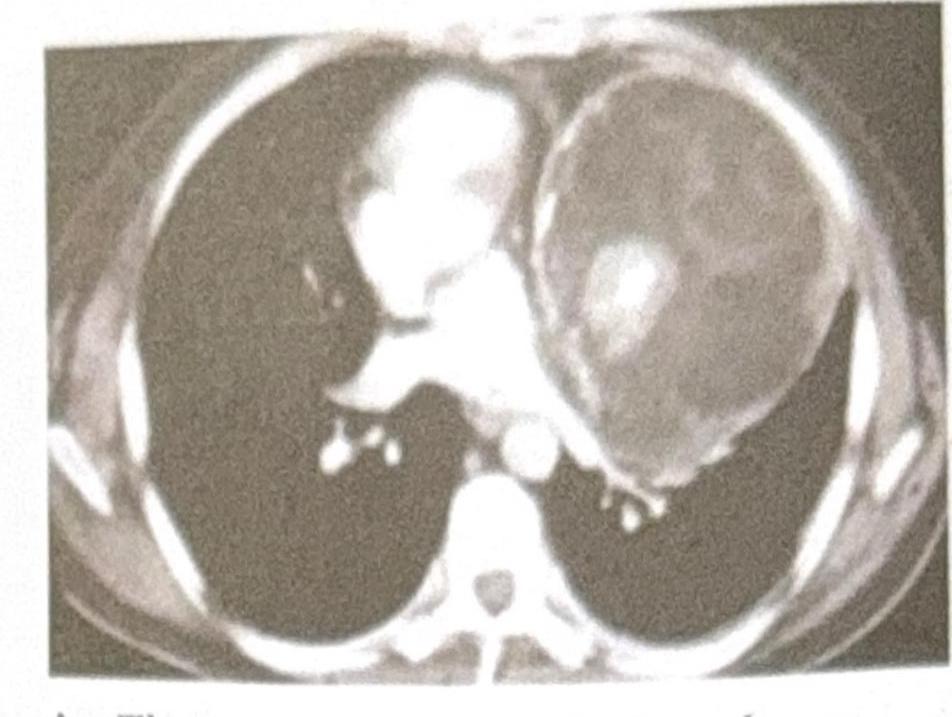

A 25-year-old male presents with chest pain and shortness of breath. A CT scan of the chest is performed, and the image provided shows a large, well-defined mass in the anterior mediastinum. The mass contains both cystic and solid components, along with areas of calcification. Based on the clinical presentation and imaging findings, what is the most likely diagnosis?

Explanation: ***Teratoma*** - The presence of a **well-defined anterior mediastinal mass** with **cystic and solid components** and **calcifications** is highly characteristic of a teratoma. - Teratomas are **germ cell tumors** containing tissues derived from all three embryonic germ layers, which explains their varied composition on imaging. *Thymoma* - While thymomas are common in the **anterior mediastinum**, they typically present as **solid masses** and calcifications are less common. - They are often associated with paraneoplastic syndromes like **myasthenia gravis**, which is not mentioned in this case. *Lymphoma* - Lymphoma in the anterior mediastinum often presents as a **lobulated, homogeneous mass**, and can be associated with **lymphadenopathy** elsewhere. - While it can be large, the specific features of cystic components and calcification are less typical for lymphoma. *Bronchogenic cyst* - Bronchogenic cysts are typically **unilocular, fluid-filled cystic lesions** and are usually found in the middle mediastinum or adjacent to the trachea/main bronchi. - They rarely contain significant solid components or calcifications, unlike the described mass.